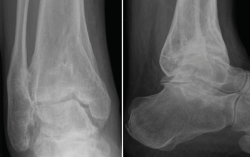

La artrodesis de tobillo sigue siendo, en la actualidad, el procedimiento quirúrgico más común para el manejo de la OA de tobillo. Como todos los procedimientos quirúrgicos, el objetivo es obtener un pie estable, plantígrado y libre de dolor. La alineación óptima para lograr estos objetivos es una flexión plantar/dorsal de 0°, valgo de 5° del retropié, 10° de rotación externa y un desplazamiento posterior del astrágalo respecto al borde anterior de la tibia de 0-10 mm(22,23). La fusión del tobillo tiene como consecuencia un incremento del gasto energético del 3% y puede alcanzar una marcha con el 90% de eficiencia durante la marcha normal(24).

En casos de deformidad severa en varo, esta debe ser reconocida y corregida de manera preoperatoria, ya que la persistencia de la alineación en varo es un factor de riesgo para la pseudoartrosis de la fusión(25). El varo provoca un bloqueo de la articulación mediotarsiana durante la etapa de despegue de la marcha, por lo que se genera una sobrecarga compensatoria en la región lateral del antepié(26). Distintos abordajes se han descrito para la fusión de tobillo: abordaje anterior, lateral transperoneo, miniartrotomía medial y lateral, artroscópico o abordaje posterior, siendo los más comunes los dos primeros. El mejor abordaje debe tener en cuenta el “ápex” de la deformidad y el estado de los tejidos blandos, así como la necesidad de extender o realizar otros abordajes para procedimientos adicionales, siempre manteniendo un puente cutáneo para reducir el riesgo de necrosis.